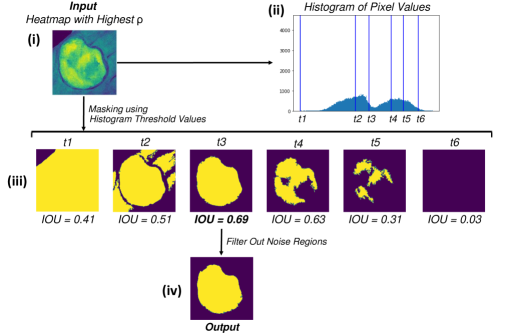

2.3.2 Segmenting high-resolution visualizations

Once a visualization/heatmap is created that highlights the burn regions in an image, it can be used for producing a segmentation mask. First, a Gaussian Mixture Model (GMM) is fitted to the pixel values of the generated visualization. Next, the points where Gaussian components meet are computed for the fitted model. We refer to these points as . Finally, the heatmap is masked using these computed points in order to create a binary segmentation of the burn regions. For every threshold value , the Intersection-Over-Union (IOU) score between the generated binary segmentation mask and the Grad-CAM heatmap is computed. The final threshold value (and therefore, the final binary mask) is selected to be the one that results in the highest IOU score. The generated binary segmentation mask then undergoes a post-processing step in order to filter out the noise regions.

Once the heatmaps with the highest correlation coefficients are selected, these high-resolution visualizations are utilized as the input to make binary segmentation masks as illustrated in Figure 4(i). The generation of masks uses Gaussian components of the maps to find thresholds (Figure 4(ii)) and subsequently uses the highest Intersection-Over-Union (IOU) values (Figure 4(iii)) between the binary masks generated and the Grad-CAM to select the final mask. The generated binary segmentation mask lastly undergoes a post-processing step in order to filter out the noise/false positive regions and produce the final BAM mask (Figure 4(iv)), which can be used for super-positioning on the input image (Figure 2b).